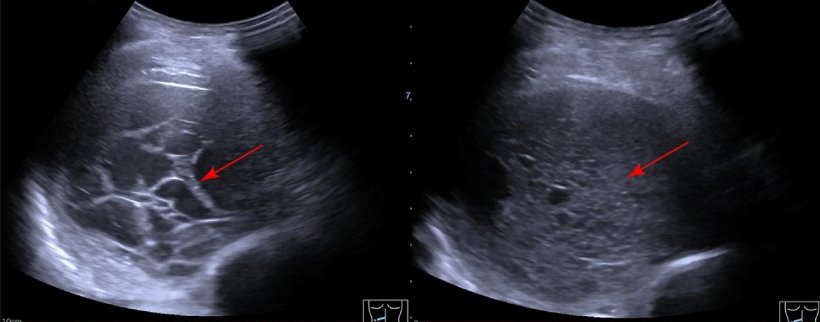

Image source: adapted from: Yang L, Wang K, Li W, Scientific Reports 2024 (CC BY 4.0)

In thoracic examinations, another advantage of ultrasound imaging comes into play: ‘Sonography clearly has the edge because examinations can be performed in real-time,’ explained Dr Trenker. Particularly when assessing thoracic wall infiltration in bronchial carcinomas, ‘the decisive factor is the respiratory-dependent fixation of the tumour, and here the sensitivity and specificity of ultrasound is clearly superior to CT imaging.’2 Ultrasound also remains the method of choice for the detection and differentiation of pleural effusions in 2025. ‘Not only can pleural effusions of just a few millilitres be detected, but they can also be differentiated more accurately,’ said the expert.3

- Yang L, Wang K, Li W, Liu D: Chest ultrasound is better than CT in identifying septated effusion of patients with pleural disease; Scientific Reports 2024; https://doi.org/10.1038/s41598-024-62807-4